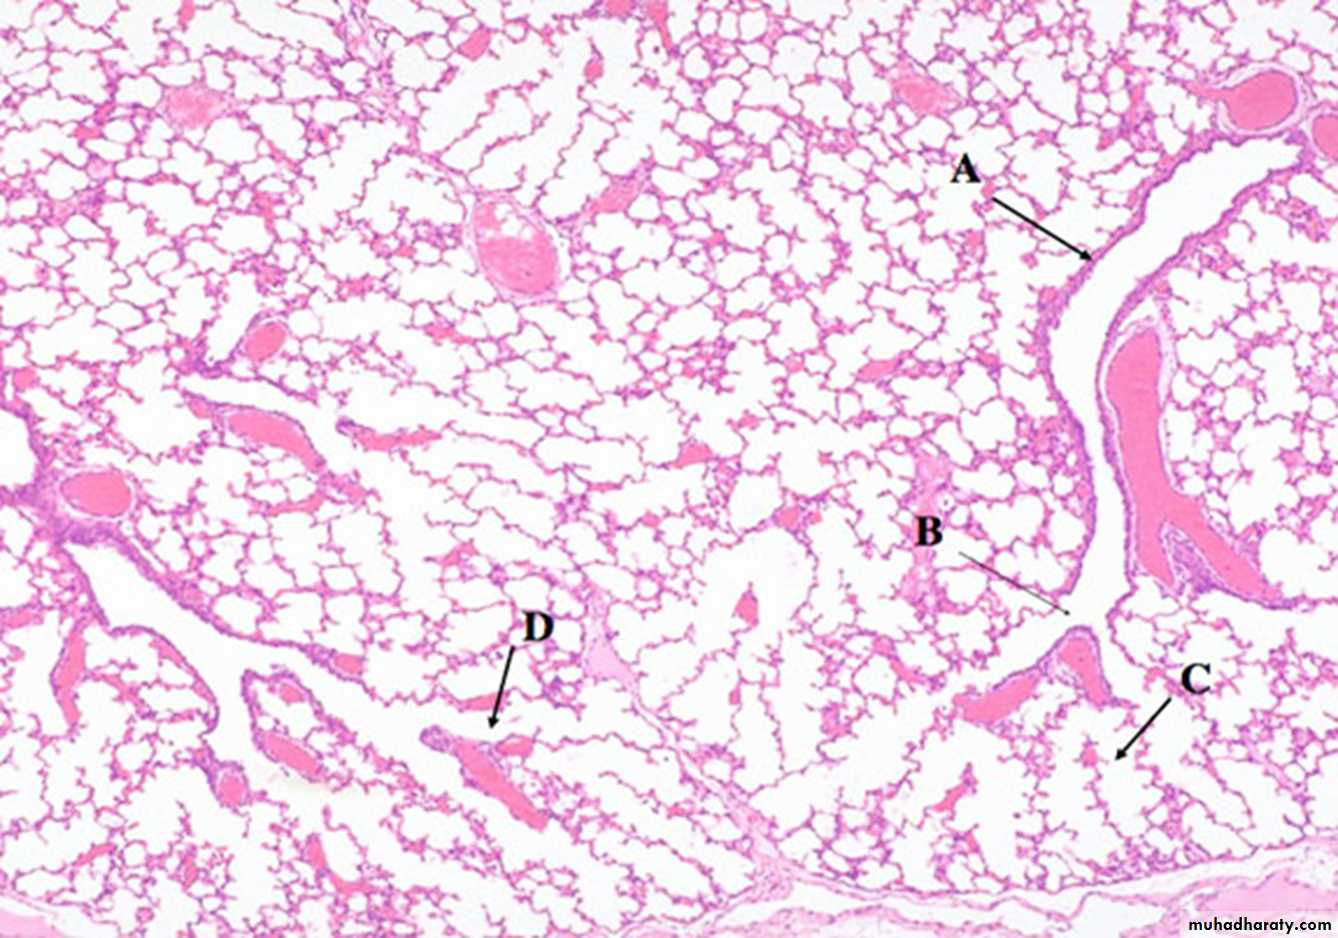

6. T. BronchioleThe respiratory airways, which facilitate gas exchange. These are located entirely within the lung .

Acinus is the functioning unit of respiratory system

1- respiratory bronchiole(B)

2- alveolar duct(D)

3- alveolar sac(C)

4- Alveoli

a lobule is composed of about 5 acini distal to a terminal bronchiole.

an acinus consists of 3 to 5 generations of respiratory bronchioles and a variable number of alveolar ducts and alveolar sacs.